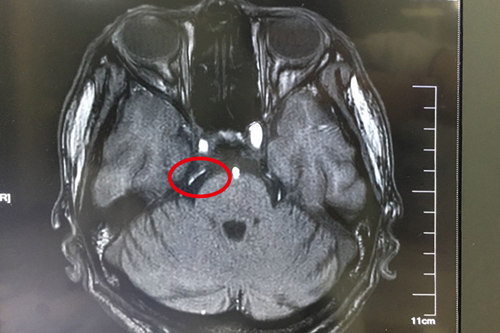

術前核磁共振顯示:雙側三叉神經(jīng)周圍見小血管與之接觸,并見騎跨

待做完各項檢查之后,神經(jīng)外科主任沈建康教授和科室其他醫(yī)生一起討論了王大爺?shù)牟∏椋懦死^發(fā)性三叉神經(jīng)痛,一致認為患者現(xiàn)在發(fā)作頻繁,吃藥已無法控制病情,手術指征明顯。待準備就緒后,8月1日下午,由沈教授親自主刀,借助德國蔡司雙熒光顯微鏡,王大爺?shù)奈⒀軠p壓術順利完成;術后8天拆線,恢復良好,現(xiàn)已順利出院。